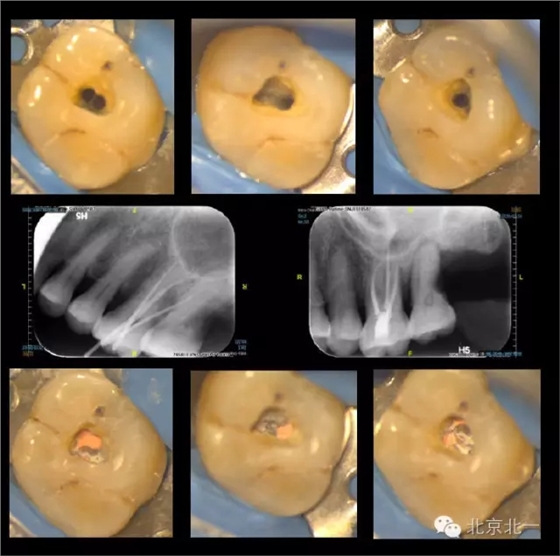

再看我們的現(xiàn)實,在我們的日常工作中,也一直期望能對微創(chuàng)開髓多有嘗試,可惜的是由于我國患者的口腔保健意識還有待提高,很多來牙髓病專科就診的患者牙體本身由于病變已沒有微創(chuàng)的可能。前段時間終于等到了這么一例牙周牙髓聯(lián)合病變,患者有著強烈的保留牙齒的愿望,但在牙周治療中并發(fā)了牙髓炎的癥狀,因此轉診至牙體牙髓??菩枰M行根管治療。

對于這個冠部牙體組織完好的病例,我們也確實想給她盡量保留健康組織,于是就開始了對這個病例的微創(chuàng)治療。

根充完成后,用樹脂對牙齒進行了充填(由于是急診患者,很遺憾忘了拍攝術前照)。